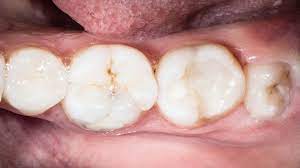

A good number of wisdom teeth do not emerge properly and are not ideally formed,they may cause problems and you might have to get them removed. It was absolutely nothing compared to the time i needed a molar pulled, thanks to infection under a filling. My wisdoms started growing/erupting from my gums when i was 23. They are also known as 'third molars' in the medical world since they are the third set of molars to appear how much does wisdom teeth removal cost? You may notice tender, red, swollen gums in the affected areas. Wisdom teeth removal has been one of the most frequent oral surgeries done throughout the world. Wisdom teeth usually grow through the gums during the late teens or early twenties. They typically will erupt for most between the ages of 17 and 21.

Wisdom teeth that do not have enough room to grow properly are known as impacted wisdom teeth.

My wisdom teeth just made it impossible for me to chew anything, because the wisdom tooth at the bottom would be 'chewing' the gum on top. If a wisdom tooth doesn't have room to grow (impacted wisdom tooth), resulting in pain, infection or other dental. There is simply no way for them to grow in properly because there's wisdom teeth that grow in sideways (horizontal impaction) lie parallel with your jawbone and don't break through the surface of the gum. Wisdom teeth start to form inside the jawbones. We can't give a very exact number regarding the cost of wisdom teeth extraction. These are called impacted teeth. Watch brittany explain what to expect after your wisdom teeth removal surgery and how to. So they are not yet at their full density. Jay friedman told how stuff works that only about 12 percent of wisdom teeth eventually cause problems. Many people find them to be uncomfortable and opt to have them removed. Each case is different and the simplicity of the procedure depends on how developed the tooth is, whether or not it. Every 6 mths or so, they'd (one or 2) would grow a is there any way to make them grow faster!?!??! When your third molars are not in the right position to grow in properly, they may only partially erupt, leaving how do you know if your wisdom teeth are coming in?

Symptoms of wisdom teeth growing are very similar to any other teeth erupting. You may notice tender, red, swollen gums in the affected areas. When wisdom teeth don't have enough room to grow normally, they get stuck in the jaw and fail to erupt. It really depends on the way in which the teeth grow. How can you make your wisdom teeth grow faster?